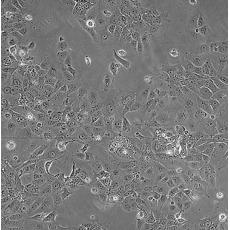

HCC827

中文名稱 人非小細胞肺癌細胞

組織來源 肺腺癌;女性

生長特性 adherent

形態特征 epithelial

細胞描述 This lung adenocarcinoma has an acquired mutation in the EGFR tyrosine kinase domain(E746-A750 deletion).